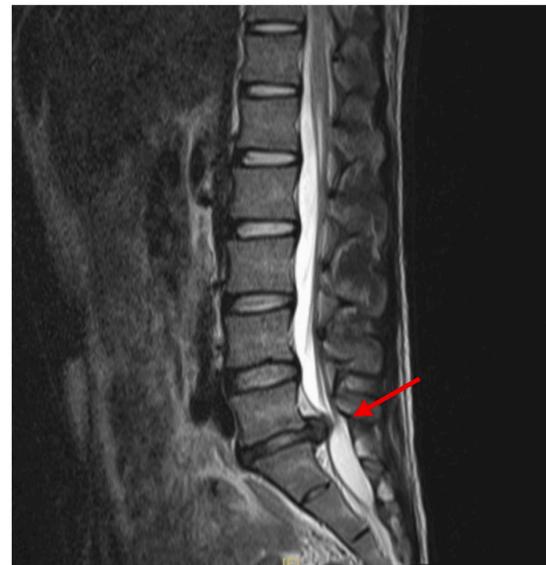

L5/S1 Disc Herniation Example: